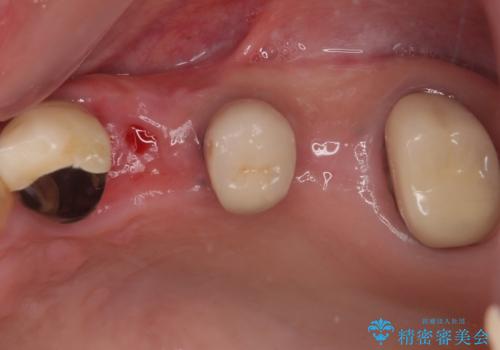

- 抜歯が必要と言われ、インプラント治療を希望して来院された患者様です。

歯がボロボロで抜歯が必要な状態であり、後方にはインプラントが埋入されているため、同様にインプラントによる補綴治療を行うこととしました。

クラウンを装着できないため、プラスチックを歯に流し込んで仮歯のようにしている状態でした。

プラスチックを外すと同時に抜歯を行い、1ヶ月ほど待機して歯肉が落ち着いたことを確認してから速やかにインプラントを埋入することとしました。